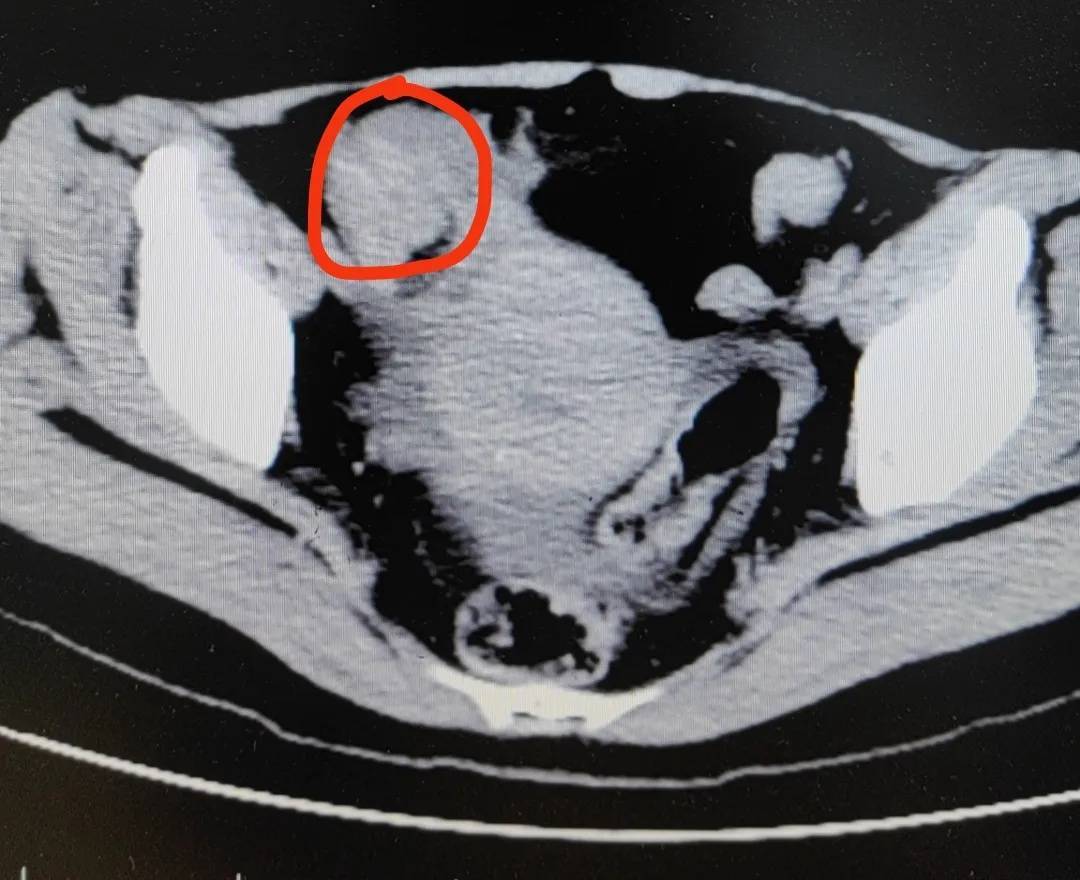

经检查,医生怀疑冯女士发生了绞窄性肠梗阻,手术从肠子里切出一堆“石头”,也就是俗称的“柿石症”,最大的直径有4厘米!